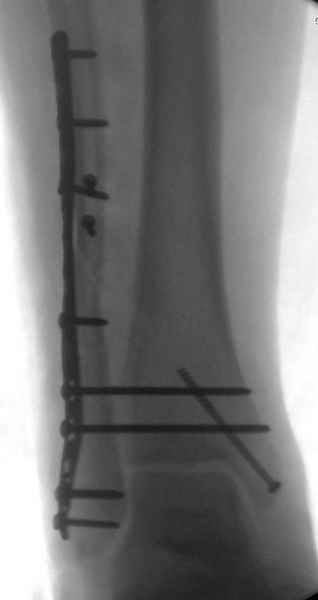

Здесь похожий случай трехнедельной давности, перелом почти сросся и была укорочена малоберцовая, на операции длину малоберцовой смогли восстановить только после того, когда проксимальнее пластины ввели шуруп и использовали его как толкатель, с помощбю дистракционого инструмента (lamina spreader).

Меньше всего волнует положение медиальной лодыжки - в любое время можно провести остео или реостеосинтез, при несращении можно просто резецировать без ущерба для движений в голеностопе. Здесь обошлись фиксацией одним 4 мм канюлированным шурупом.